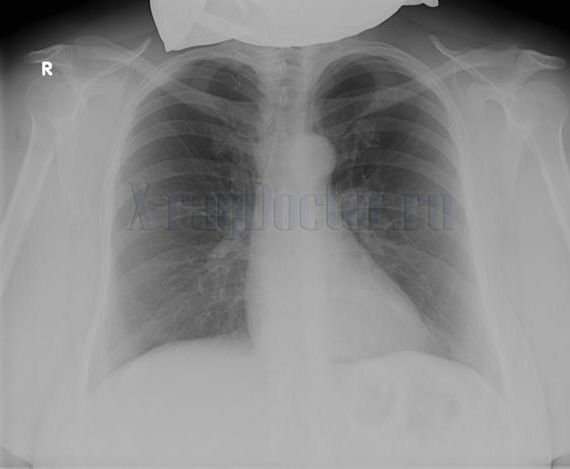

В заключение, чтобы «набить» глаз, приводим нормальную рентгенограмму легких для сравнения.

Несмотря на то что экссудативный плеврит на рентгенограмме визуализируется четко, нельзя упускать из виду, что он может быть последствием других заболеваний (опухолей, туберкулеза). Стандартом при выявлении заболеваний легких является рентгенография органов грудной клетки в двух проекциях, и ее необходимо выполнять.